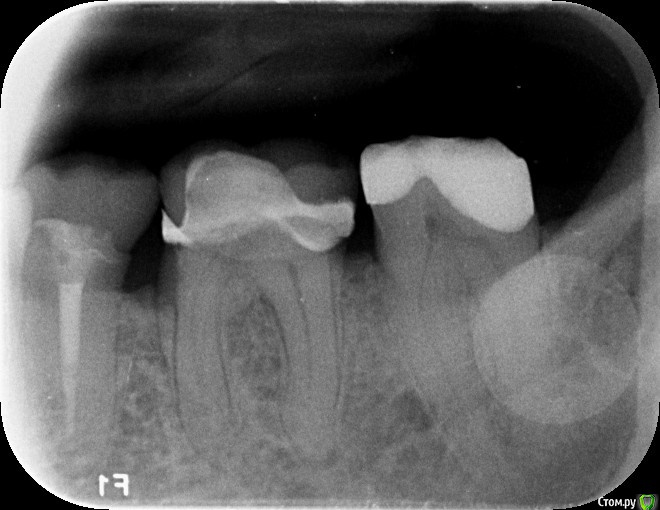

Stilos1 Опубликовано 3 августа, 2019 Поделиться Опубликовано 3 августа, 2019 Можно ли сказать, сколько каналов этой семерке? Ссылка на комментарий

___49___ Опубликовано 3 августа, 2019 Поделиться Опубликовано 3 августа, 2019 Можно ли сказать, сколько каналов этой семерке?со 100% уверенностью нет. данный снимок несет до 60% информации, как следствие можно лишь предположить сколько тут каналов с 60% точностью . альтернативный метод исследования КТ - более 90% достоверной информации . Ссылка на комментарий

DmitrySH Опубликовано 3 августа, 2019 Поделиться Опубликовано 3 августа, 2019 3 есть.Возможно наличие 4-го 1 Ссылка на комментарий